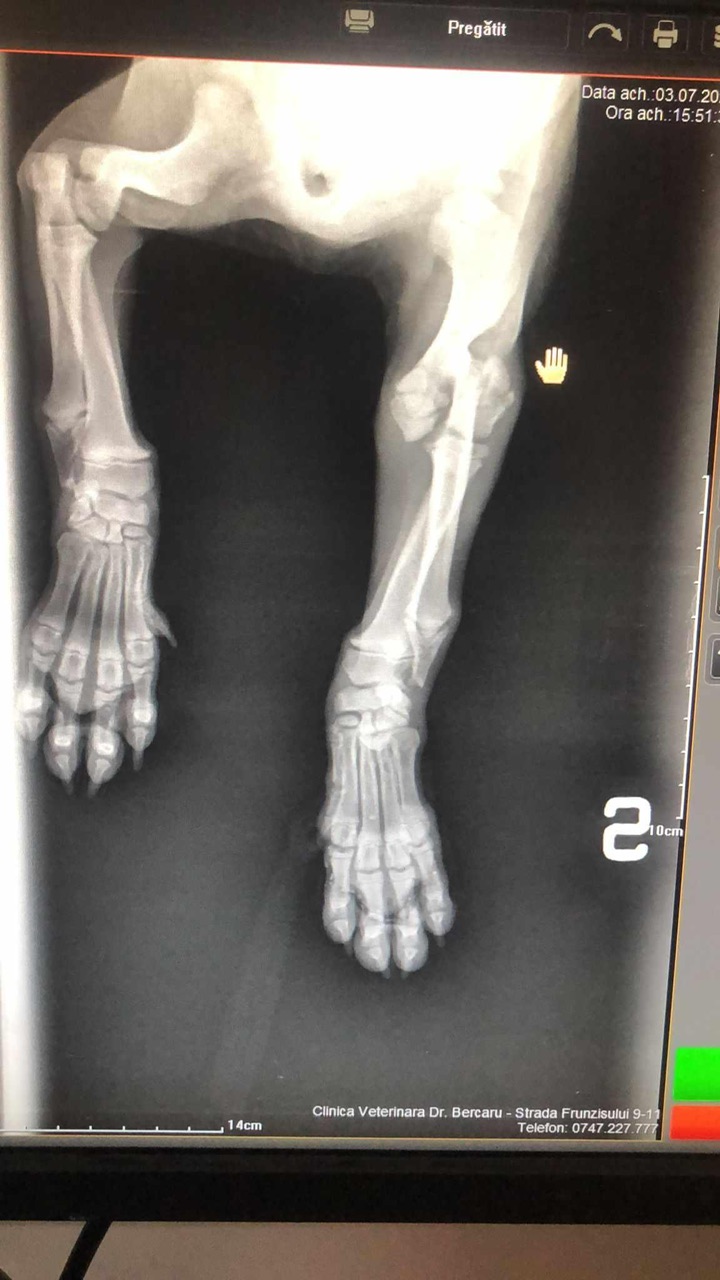

Update 03-07-2024 : Little Jay is naar de kliniek in Boekarest gebracht. Op de X-ray was te zien dat het bovenarmpootje is gebroken. Little Jay wordt zo spoedig mogelijk geopereerd.